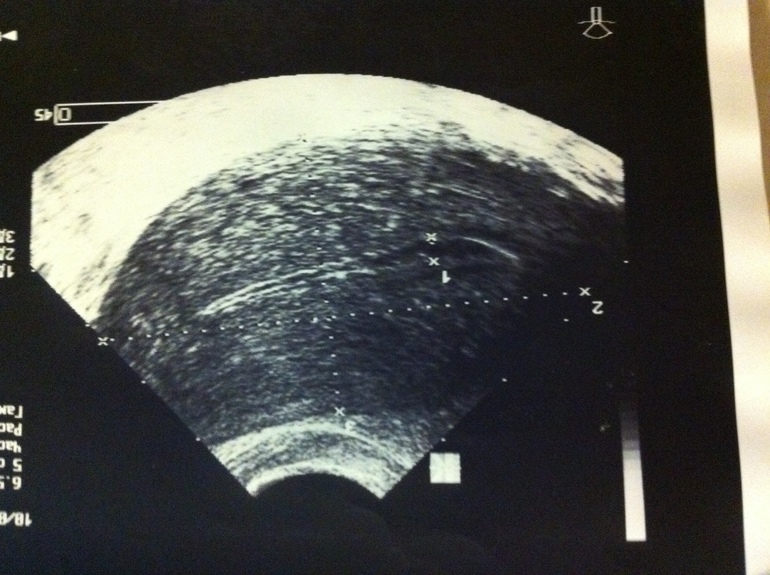

два разных УЗИ, это матка, обычно там крестики и черточки, о которых я говорила)

на фото обычно есть крестики...ими отмечают длину, ширину и т.д. посмотрите, просто качество фото не очень и я не вижу.